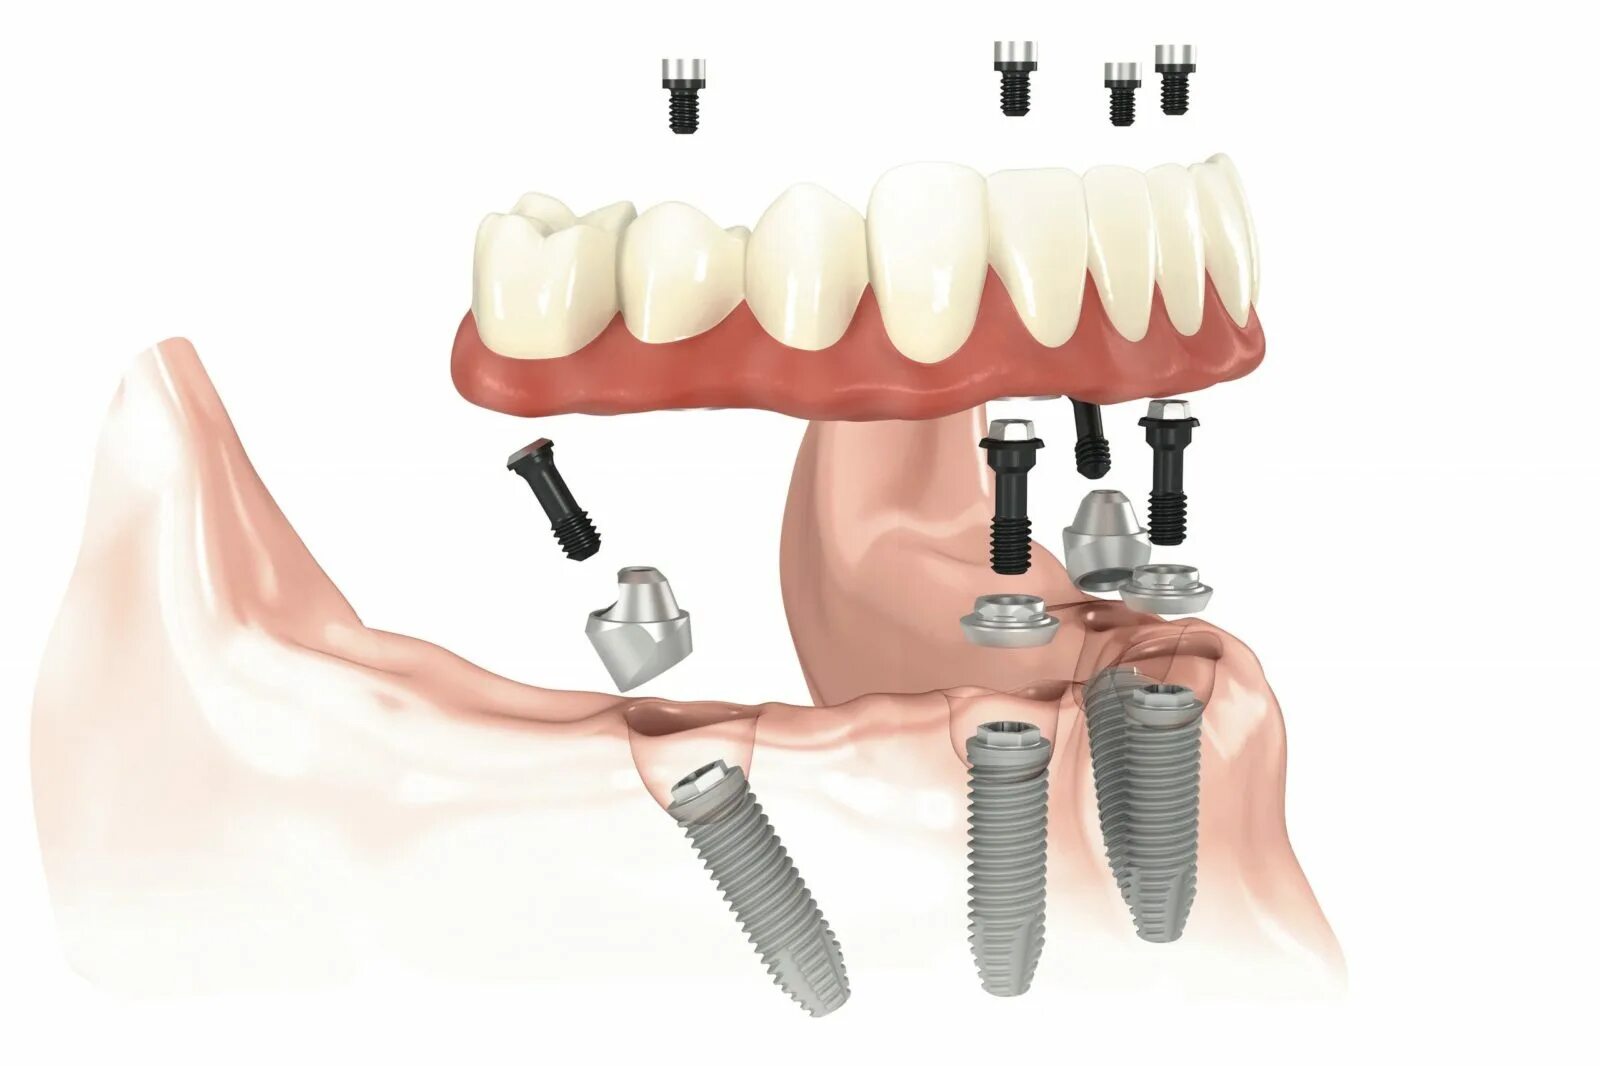

All in установка